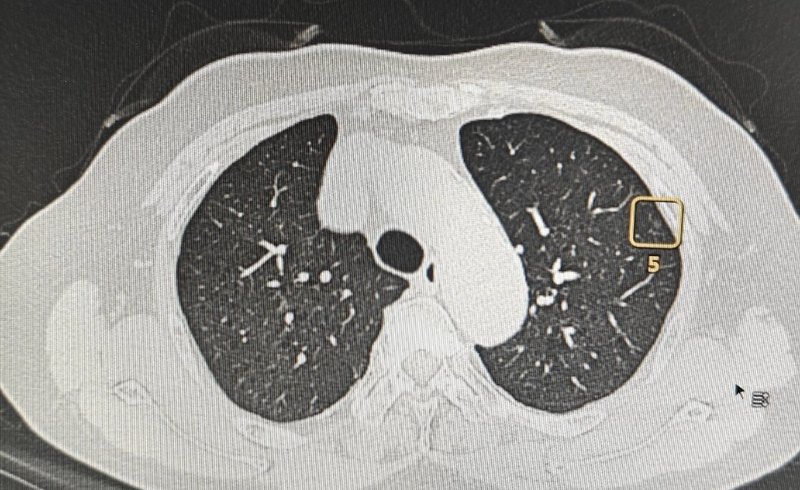

現(xiàn)在拍胸部CT的機(jī)會越來越多,所以發(fā)現(xiàn)肺磨玻璃結(jié)節(jié)也就是我們常說的GGN的朋友也越來越多了。作為一名肺外科醫(yī)生,我平時治療最多的疾病就是肺磨玻璃結(jié)節(jié)。有些朋友因?yàn)榘l(fā)現(xiàn)了自己肺里有磨玻璃結(jié)節(jié),所以平時在家研究,也會向我這樣的專業(yè)人士提出各樣的問題。有一個問題是,如果一個肺磨玻璃結(jié)節(jié)最終確診為浸潤性肺腺癌,那它是由微浸潤肺腺癌發(fā)展來的嗎?回答這個問題之前,我們先來看一個在我這里做手術(shù)的具體病例,這是一位中年女士,肺里邊有三個磨玻璃結(jié)節(jié),大的一個直徑10mm,小兩個的直徑都是6mm。我把這三個磨玻璃結(jié)節(jié)切下來之后的病理顯示,大的是浸潤性肺腺癌,兩個小的顯示的是微浸潤肺腺癌。有些朋友不理解,我舉得這個病例和這個問題的答案有什么關(guān)系?我想告訴大家的是,這三個肺磨玻璃結(jié)節(jié)的質(zhì)地都是一樣,大的現(xiàn)在是浸潤性肺腺癌,小的是微浸潤肺腺癌。如果現(xiàn)在不做手術(shù),在將來的發(fā)展過程中,小的隨著直徑的增長,也會變成浸潤性肺腺癌。